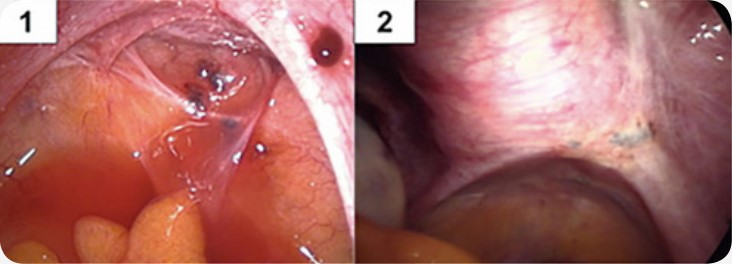

São lesões espalhadas na superfície do interior do abdômen. Podem estar disseminadas atingindo até mesmo o diafragma. Embora sejam superficiais, muitas vezes estão localizadas sobre órgãos nobres como no intestino, bexiga e ureter e, por isto os cuidados cirúrgicos devem ser bem observados para que se evitem complicações. Os sintomas mais comuns são: cólica, menstruação irregular e infertilidade. O exame clínico não apresenta alterações importantes, o ultrassom não demonstra imagens características e os marcadores que podem sugerir a presença da doença, dosados no sangue (CA125 e SAA) podem ou não estar alterados. O diagnóstico conclusivo e o tratamento são feitos pela videolaparoscopia.

1: lesão vermelha; 2 e 4: lesões negras; 3: lesão branca